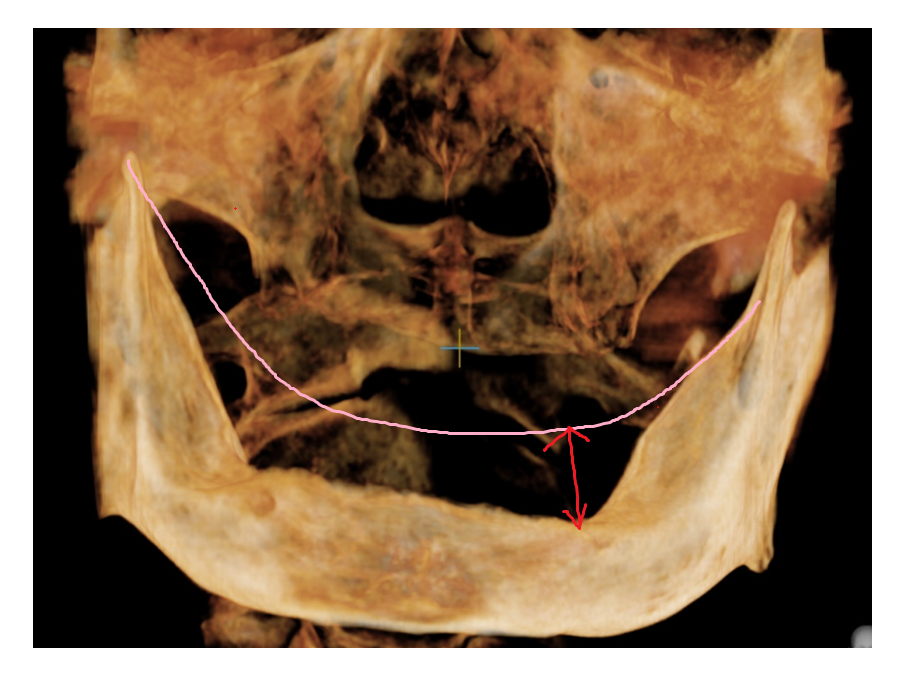

첫번째, 치조골 흡수가 심한 경우

틀니를 오래 낀 경우나

치아가 빠지고 시간이 오래 경과된 경우입니다.

임플란트를 어금니에 심기 위해서는

최소 8-10mm 길이가 필요합니다.

뼈 흡수가 심하게 되면

필요한 깊이만큼의 임플란트를 심지 못하게 되는데

이는 임플란트 수명에도 영향을 끼치게 됩니다.

짧은 임플란트는 씹는 힘을 온전히 견디기 어렵게 되거든요.